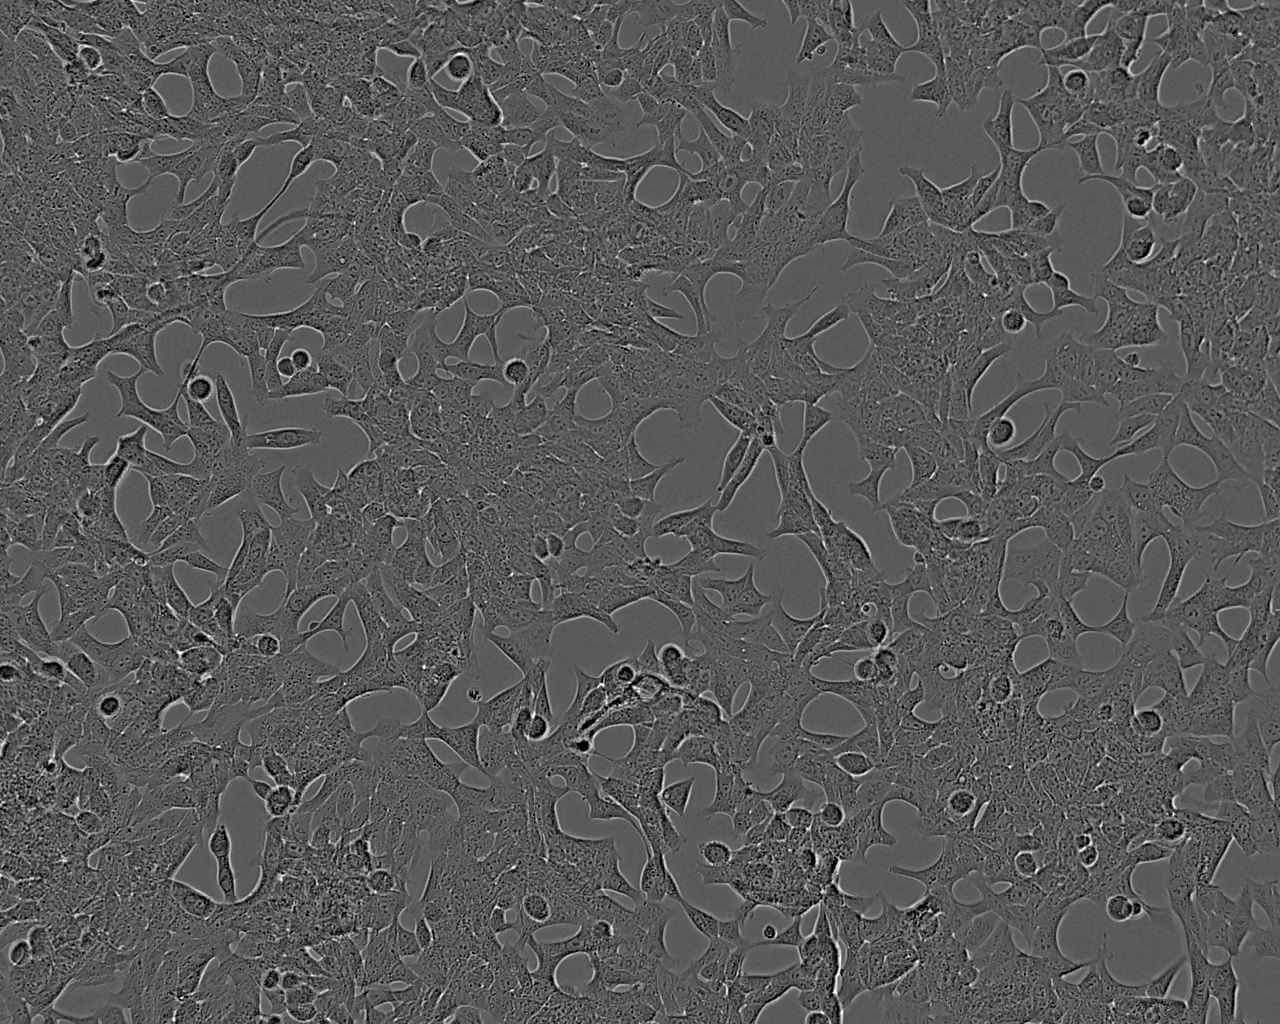

Derived from a metastasis at the left supraclavicular lymph node of a 50 year old patient with a confirmed diagnosis of metastatic prostate carcinoma. Growth and acid phosphatase production is affected by 5-alpha-dihydrotestosterone. They do not form a uniform monolayer and attach only lightly to the substrate. When shipped, cells detach from flask and can either be incubated 24-48 hours to allow attachment or be collected by centrifugation (150xg, 15 minutes) and reseeded.

Split sub-confluent cultures (70-80%) 1:3 to 1:6 using 0.05% trypsin or trypsin/EDTA; 5% CO₂; 37°C.i.e. seeding at 3-4 x 10,000 cells/cm² Cells grow slowly in clusters and can be disaggregated by repeated pipetting. After subculture cells may take up to 48 hours to reattach. Do not disturb during this period. Medium is rapidly acidified, therefore change twice per week.